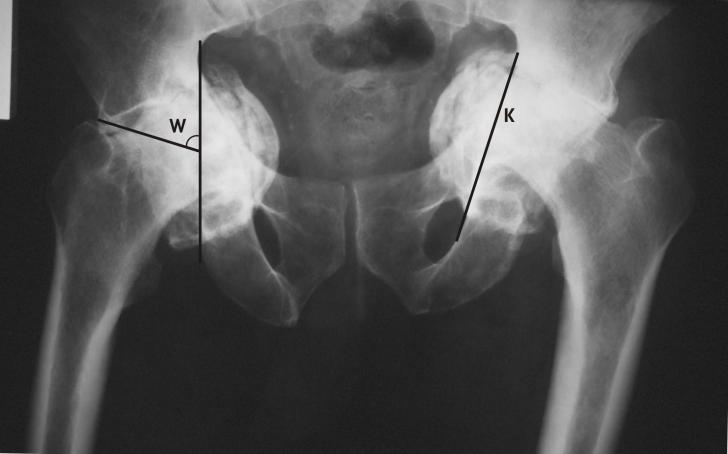

Protruzie acetabulara cu coxartroza bilaterala - prezentare de caz

PROTRUZIE ACETABULARA CU COXARTROZA BILATERALA - PREZENTARE DE CAZ PRIMARY TOTAL HIP ARTHROPLASTY IN BILATERAL ACETABULAR PROTRUSION (Abstract): Acetabular protrusion is a clinical entity consisting of deepening of the acetabulum and cCiteste tot ... 2493 cuvinte

Dimensiune medie

+ cu poze |